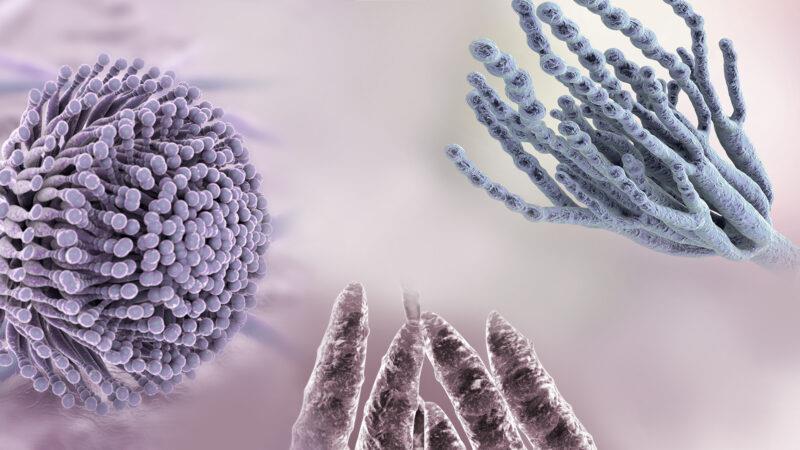

قیمت: 22٬000 تومان - دسته بندی فایل: علوم پزشکیپاورپوینت مایکوتوکسین ها

فروش ویژه پاور پوینت حرفه ای مایکوتوکسین ها با تخفیف استثنایی فقط 49 هزار تومان تعداد اسلاید: 15 اسلاید